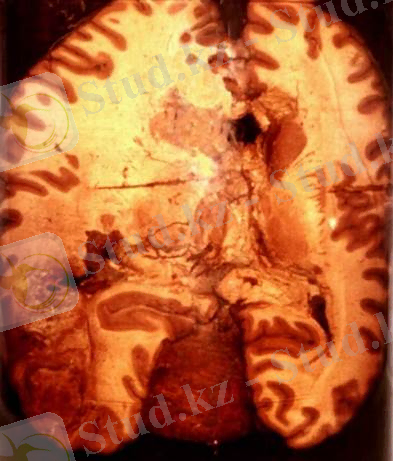

Ми инфаркты. ми қан тамырларының окклюзиясына, тромбо-зына, эмболиясына байланысты дамиды. Ми инфарктының даму-ыңда ми қан тамырлары арасындағы коллатералдық жолдардың маңызы зор, себебі ми қан тамырлары бір-бірімен өте тығыз бай-ланысқан. Вимизий шеңбері осы жолдарды байланыстырып түра-ды. Мидағы инфаркт негізінен мидың орта артериясының бассейнінде дамиды. Ми артерияларының окклюзиясы (тарылып қалуы, тығындалуы) негізінен атеросклероздық өзгерістерге байланысты. Атеросклероздық өзгерістер ми артерияларыңда ғана емес, омыртқа артериясында (a. vertebralis) және ішкі үйқы артериясын-да да дамуы мүмкін. Пайда болған атеросклероздық табақшалар артериялар саңылауын тарылтып немесе бүтіндей бітеп тастайды.

Морфологиясы бойынша инфаркттың ақ (ишемиялық), қызыл (геморрагиялық) және аралас түрлерін ажыратады. Мидың ақ инфаркты (ишемиялық инсульт) дамыған аймақтарда алғашқы 6-12 сағатта ісіну, жүмсару белгілері пайда болады. 1 тәуліктен кейін мидың ісінген жерлері өте болбыр, кесіп қарағанда пышаққа жа-бысатын болып қалады. Инфаркт аймағыңда мидың сүр және ақ заттары арасындағы шекара жойылады. Тек 48-72 сағаттан кейін ғана ишемиялық некроз ошақтары ісіп, былжырап, ыдырап, аньгқ көрінеді. Микроскоппен қарағанда инфаркт аймағында нерв жасушаларының хроматолизі, пикнозы, ишемиялық өзгерістері, некрозы көрінеді. Нерв аксондары бөлшектеніп кетіп, олардың миелиндік қабығы ьдырайды. 48 сағаттан соң инфаркт аймағында лейкоциттёр пайда болады.